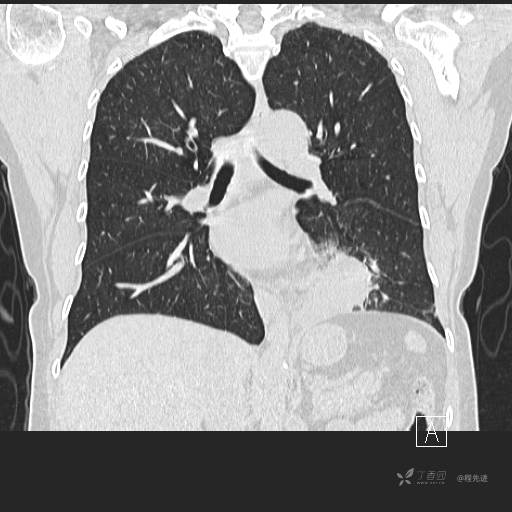

冠状位重建

CT值:平扫:31HU,动脉期:74HU,静脉期:84HU